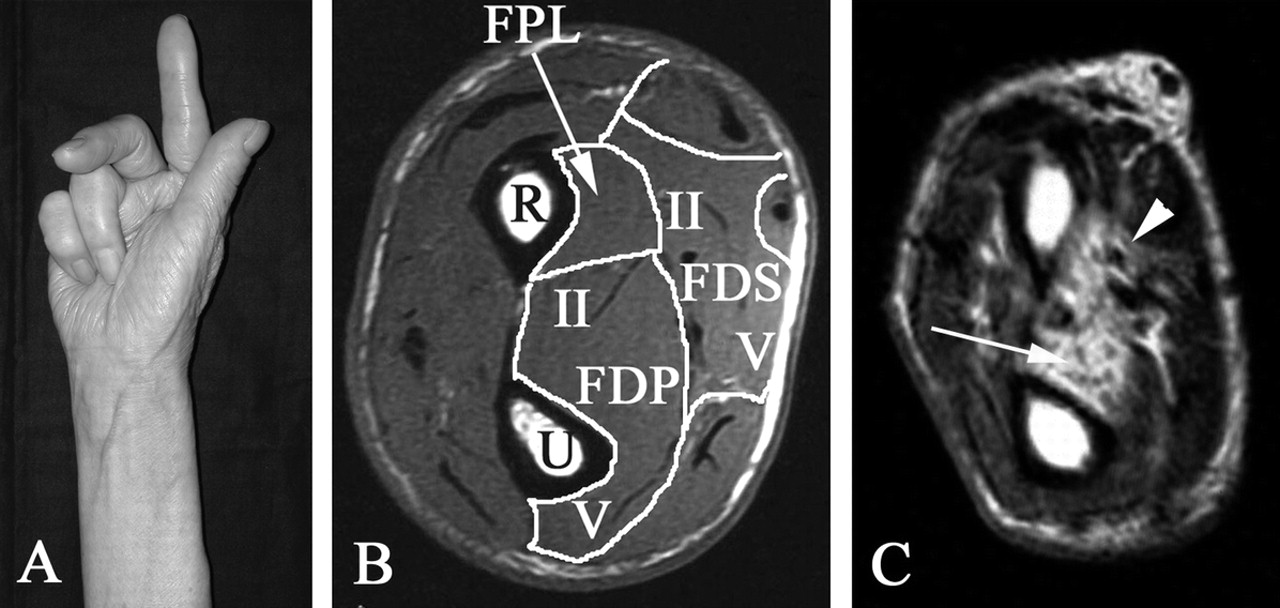

一个72岁的女人,零星的包涵体肌炎表现为缓慢进行性乏力手指屈肌和下肢近端。她无法flex双边第一位和第二位在近端和远端指间关节,而第四和第五位数相对幸免(图,一个)。感觉障碍和挛缩被观察到。每个数字之间的差异,肌肉无力与脂肪的渗透,显示T1 hyperintensity,长屈全身和特定区域内profundus屈肌腱牵向前和superficialis屈肌腱牵向前1(图中,B和C)。这些观察表明,疾病过程可能进展过程磕磕绊绊,不广泛,涉及肌肉内包涵体肌炎。